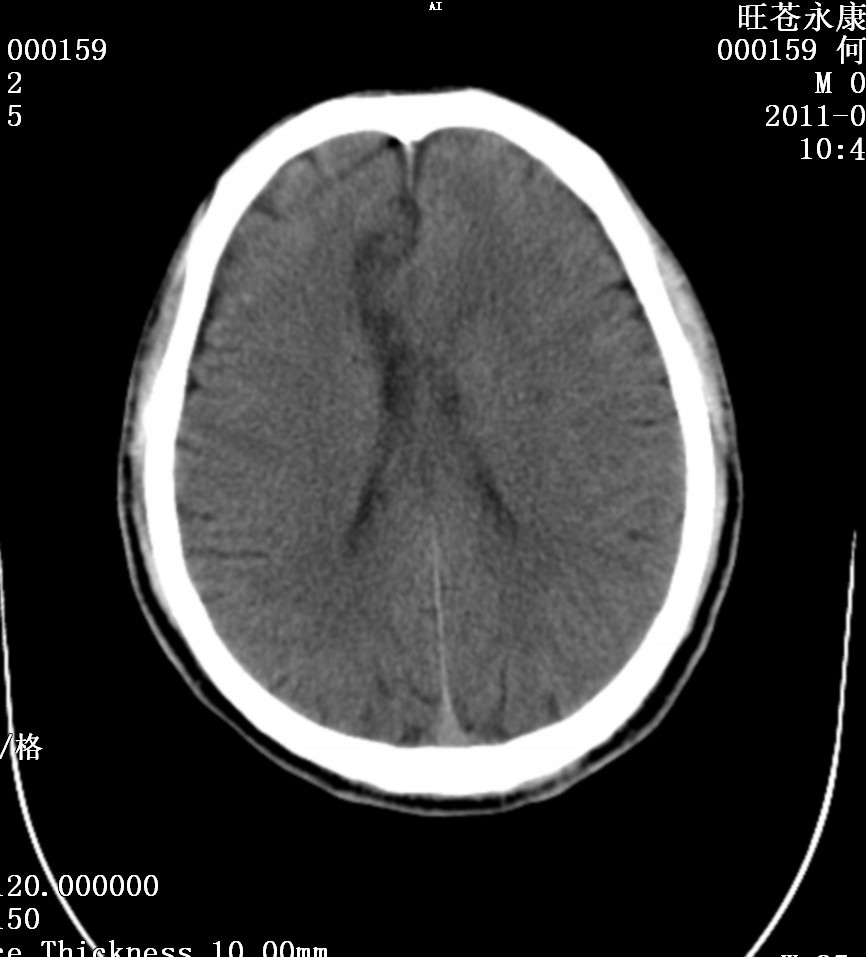

大家帮忙看看,男.69岁,下肢麻木